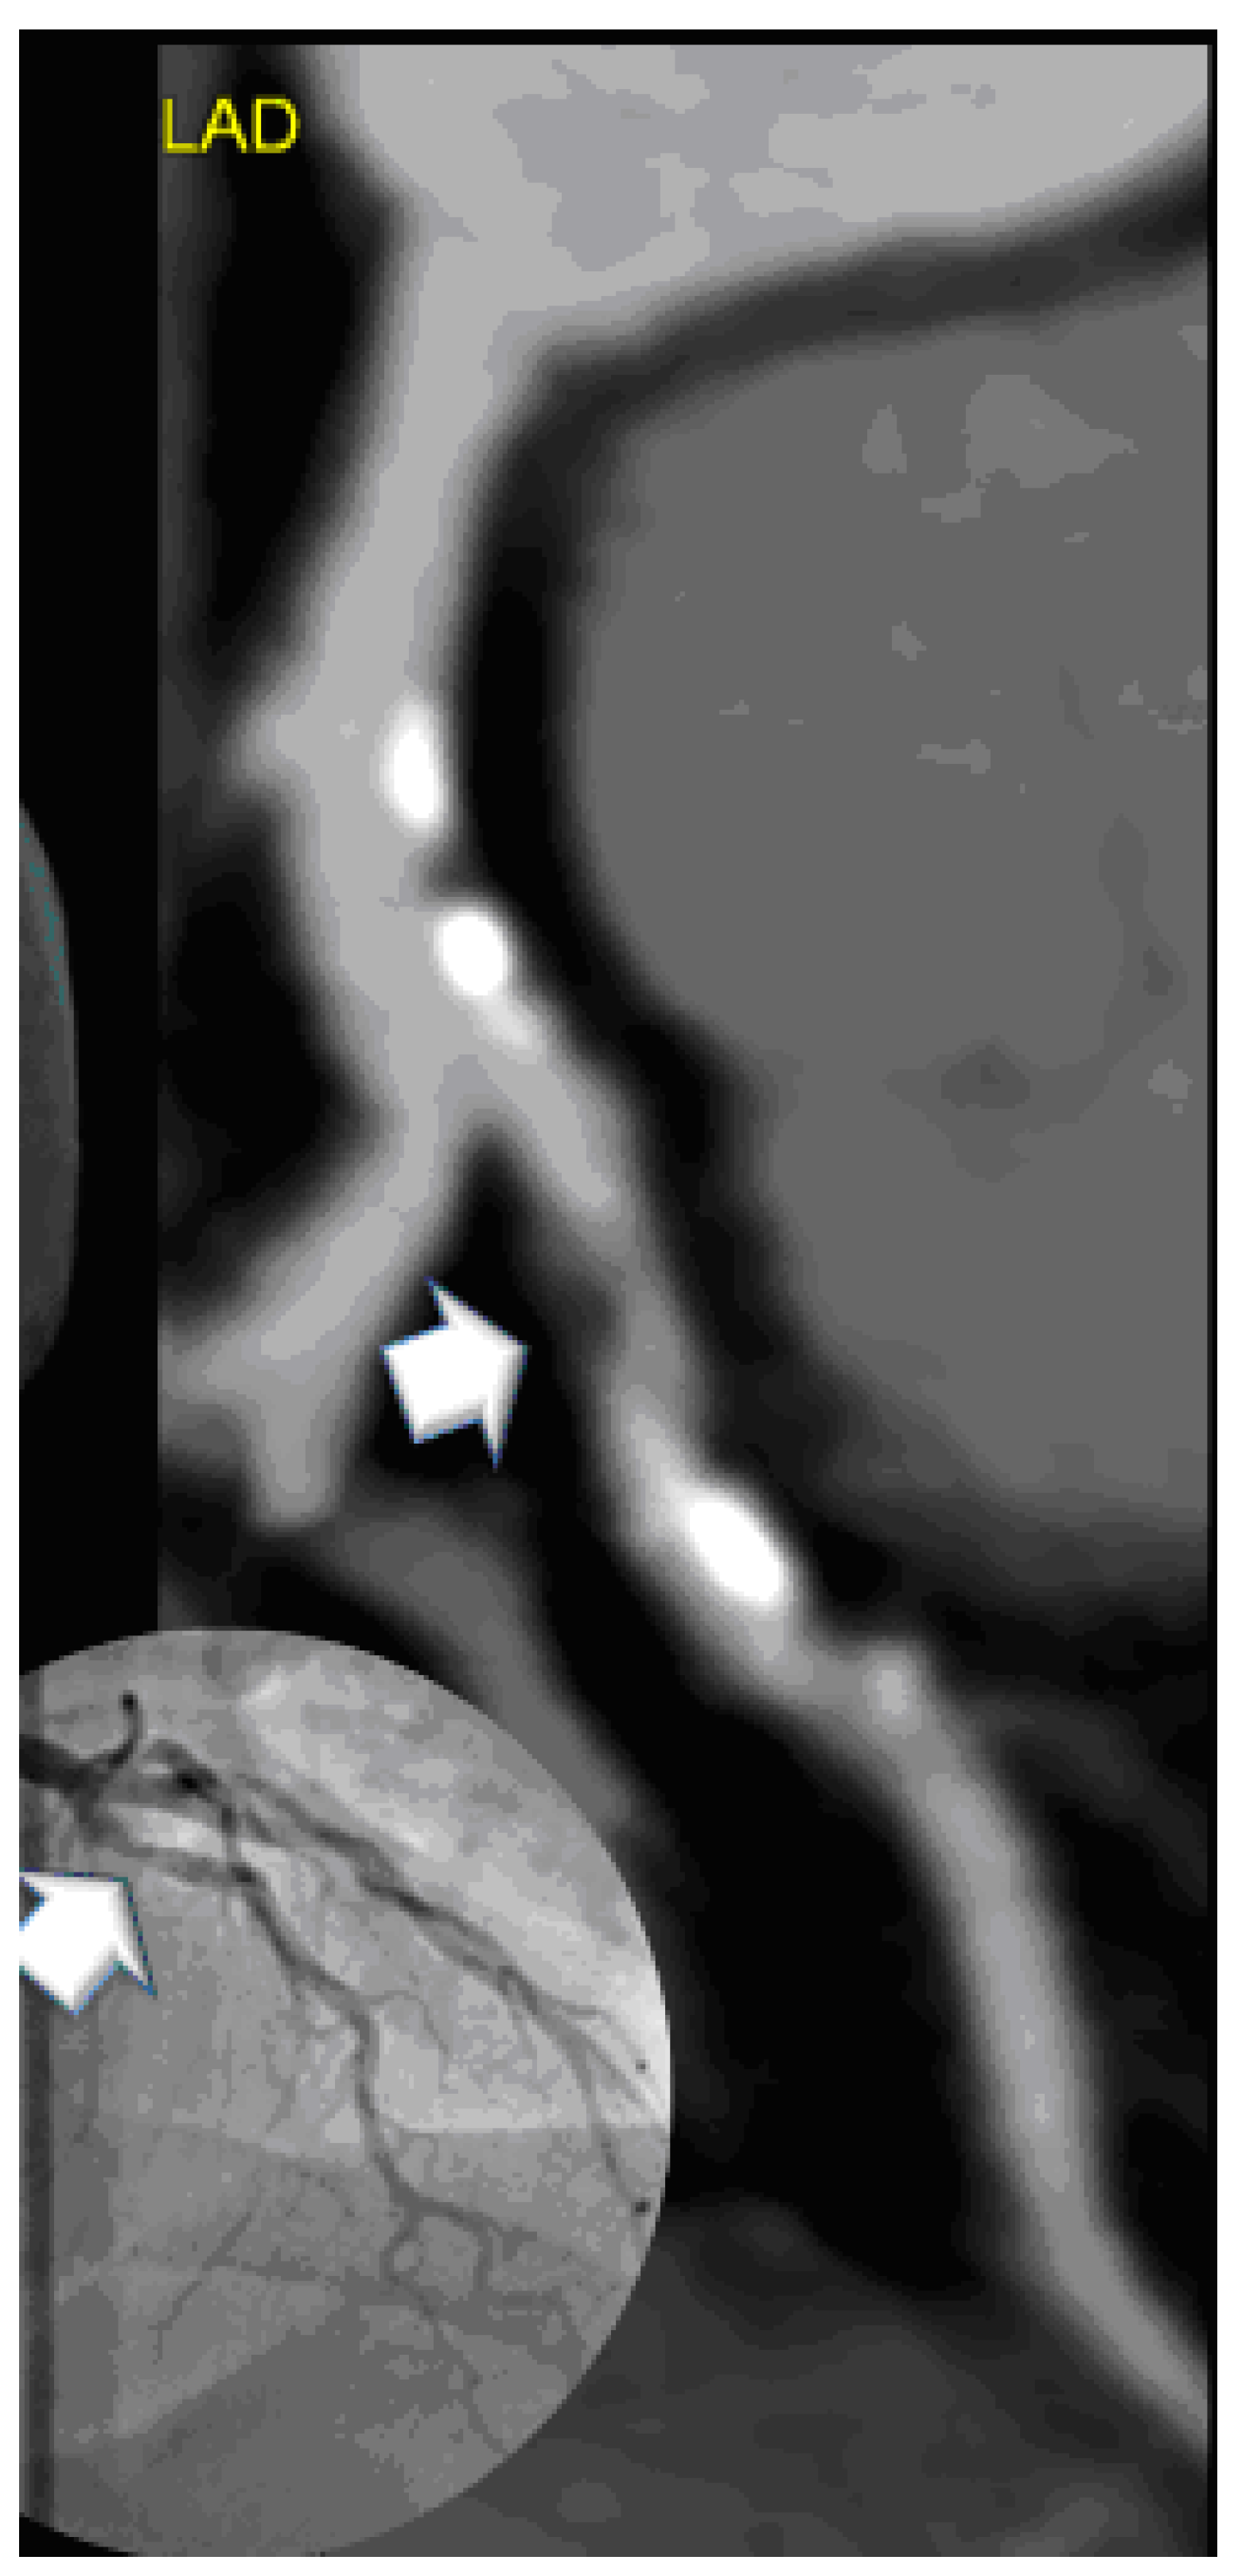

- Low attenuation plaque, hypodense to the artery lumen, was screened by utilizing the “pixel-lens” for the lowest CT-density (HU) area [18], and then a ROI was drawn as large as possible, while sparing areas affected by motion, beam hardening or partial volume artifacts. The HU ROI was measured on 3 consecutive images (1 mm slice thickness). Low attenuation plaque was defined as “non-calcified” if density was below 150 HU [27];

- Napkin Ring Sign was defined [17] as low attenuation plaque with a hyperdense rim and hypodense LAP core;